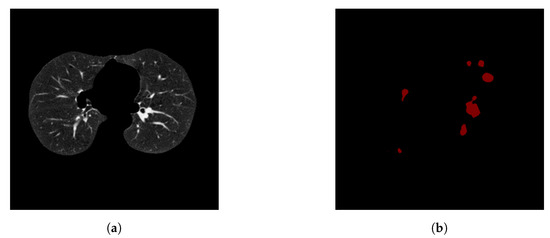

After image preprocessing, we detect the nodules on this reduced area. The task of detecting nodules is very challenging because the nodules can be placed either inside the lungs or on the walls, and they are are very hard to discriminate from shadows, vessels, and ribs. First, we extract the nodules regions from the LUNA dataset in images as a mask, as shown in Figure 4. The masks and segmented lung images are fed into a CNN. The input to the model is a single slice, and the output is the corresponding ground truth binary mask showing nodule locations. We are using Deeplab-V3 plus that is described in Figure 5. Google has extended DeepLab-V3 plus to include a simple decoder module to enhance the results of segmentation, mainly along the boundaries of the object.

Figure 4. Two examples for a training pair: the input images after segmenting the parenchyma and the ground-truth binary nodule mask.